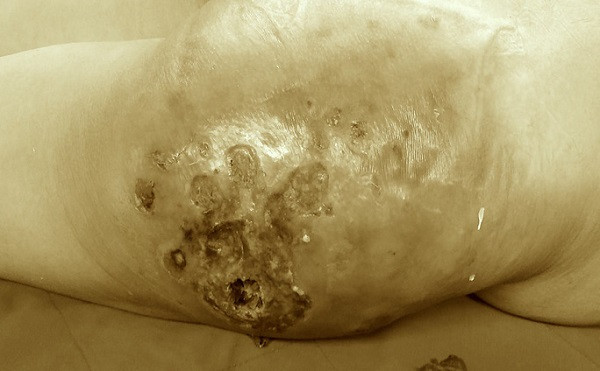

"Vòng 3" của bệnh nhân bị hoại tử, loét do bơm silicon làm đẹp

Theo thông tin từ Bệnh viện Trung ương Quân đội 108 (Bệnh viện 108), nữ bệnh nhân 45 tuổi kể trên nhập viện trong tình trạng vùng mông căng cứng, khó chịu, loét.

Qua thăm khám, các bác sĩ Bệnh viện 108 chẩn đoán, bệnh nhân bị hoại tử diện rộng da, mô mỡ vùng tiêm, viêm lan tỏa bẹn đùi. Bệnh nhân được mổ cấp cứu nạo vét ra khoảng 2.500 cc (khoảng 2,5 lít) tổ chức hoại tử và dịch mủ.

Theo PGS-TS Vũ Ngọc Lâm, Giám đốc Trung tâm Phẫu thuật sọ mặt và tạo hình - Bệnh viện 108, dù được điều trị ngay sau khi nhập viện nhưng chắc chắn mông của bệnh nhân sẽ bị biến dạng.